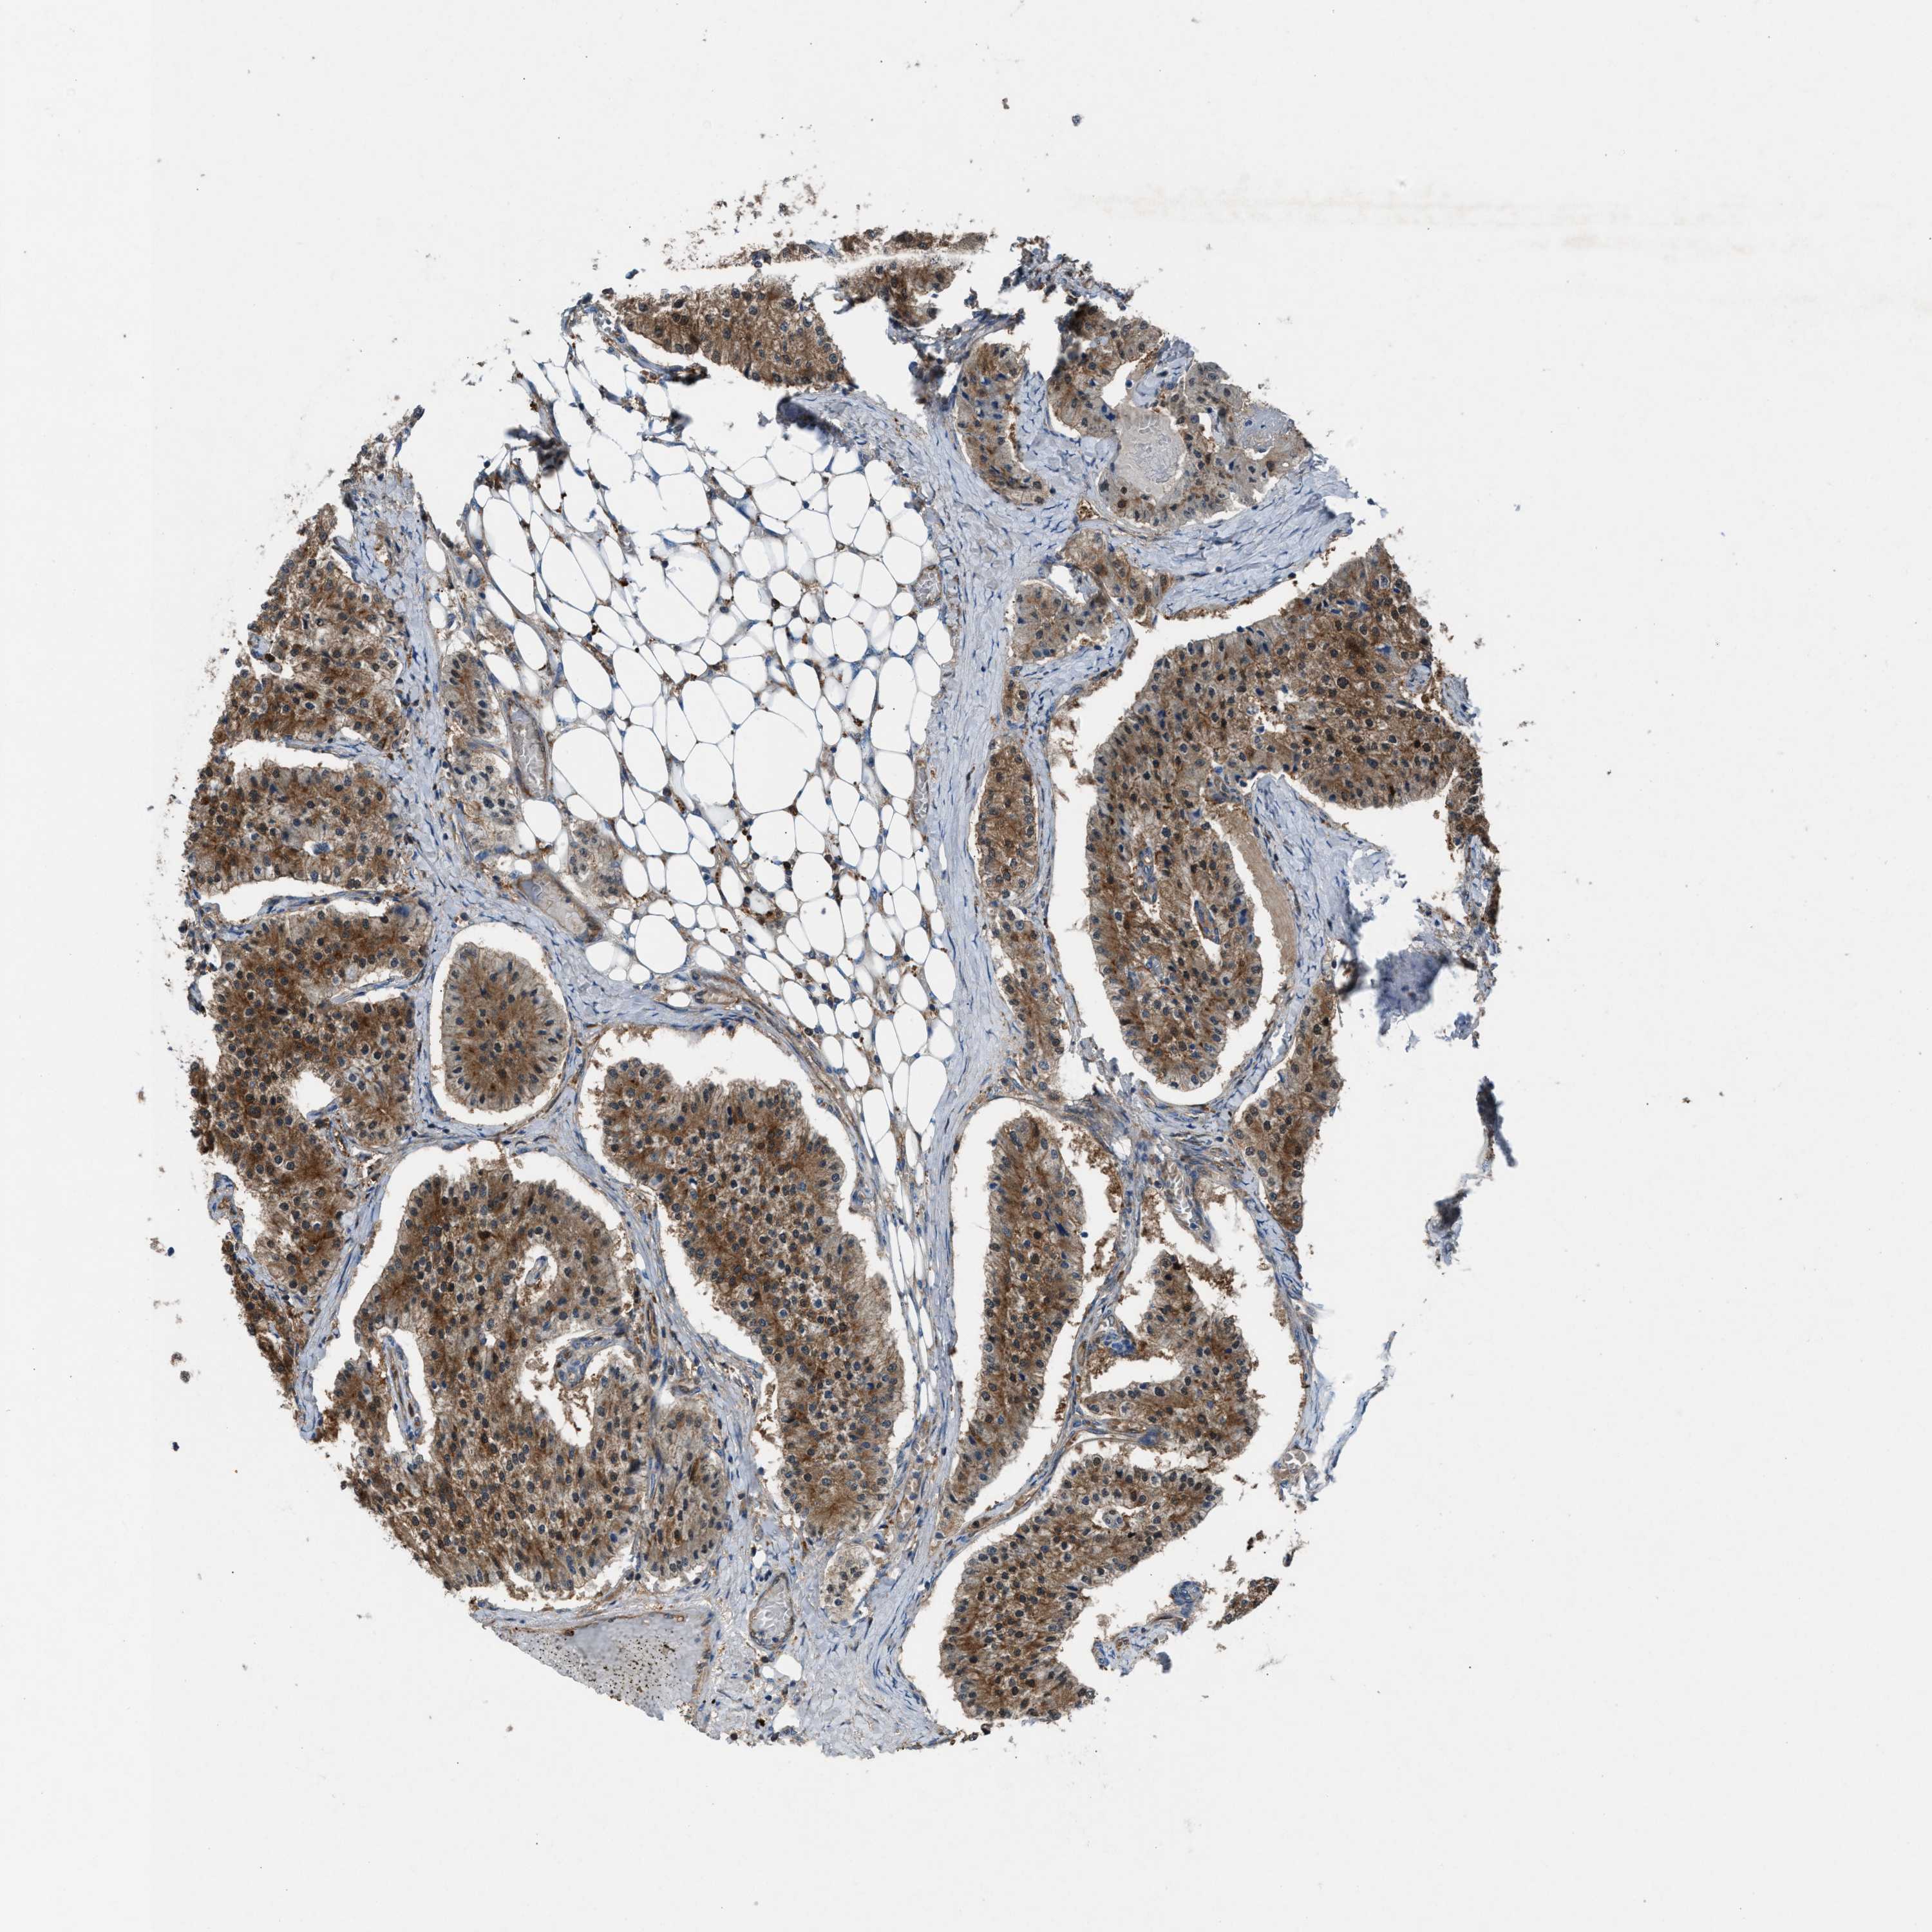

CARCINOID - Protein expressioni

A mouse-over function shows sample information and annotation data. Click on an image to view it in a full screen mode. Samples can be filtered based on level of antibody staining by selecting one or several of the following categories: high, medium, low and not detected. The assay and annotation is described here.

Antibody stainingi

Antibody staining in the annotated cell types in the current human tissue is reported as not detected, low, medium, or high, based on conventional immunohistochemistry profiling in selected tissues. This score is based on the combination of the staining intensity and fraction of stained cells.

Each image is clickable and will lead to virtual microscopy that enables deeper exploration of all samples and also displays staining intensity scores, fraction scores and subcellular localization as well as patient and tissue information for each sample.

Antibody HPA021545

Antibody HPA021849

Staining

High

Medium

Low

Not detected

Intensity

Strong

Moderate

Weak

Negative

Quantity

>75%

75%-25%

<25%

None

Location

Nuclear

Cytoplasmic/membranous

Cytoplasmic/membranous,nuclear

Carcinoid, malignant, NOS

Carcinoma, NOS